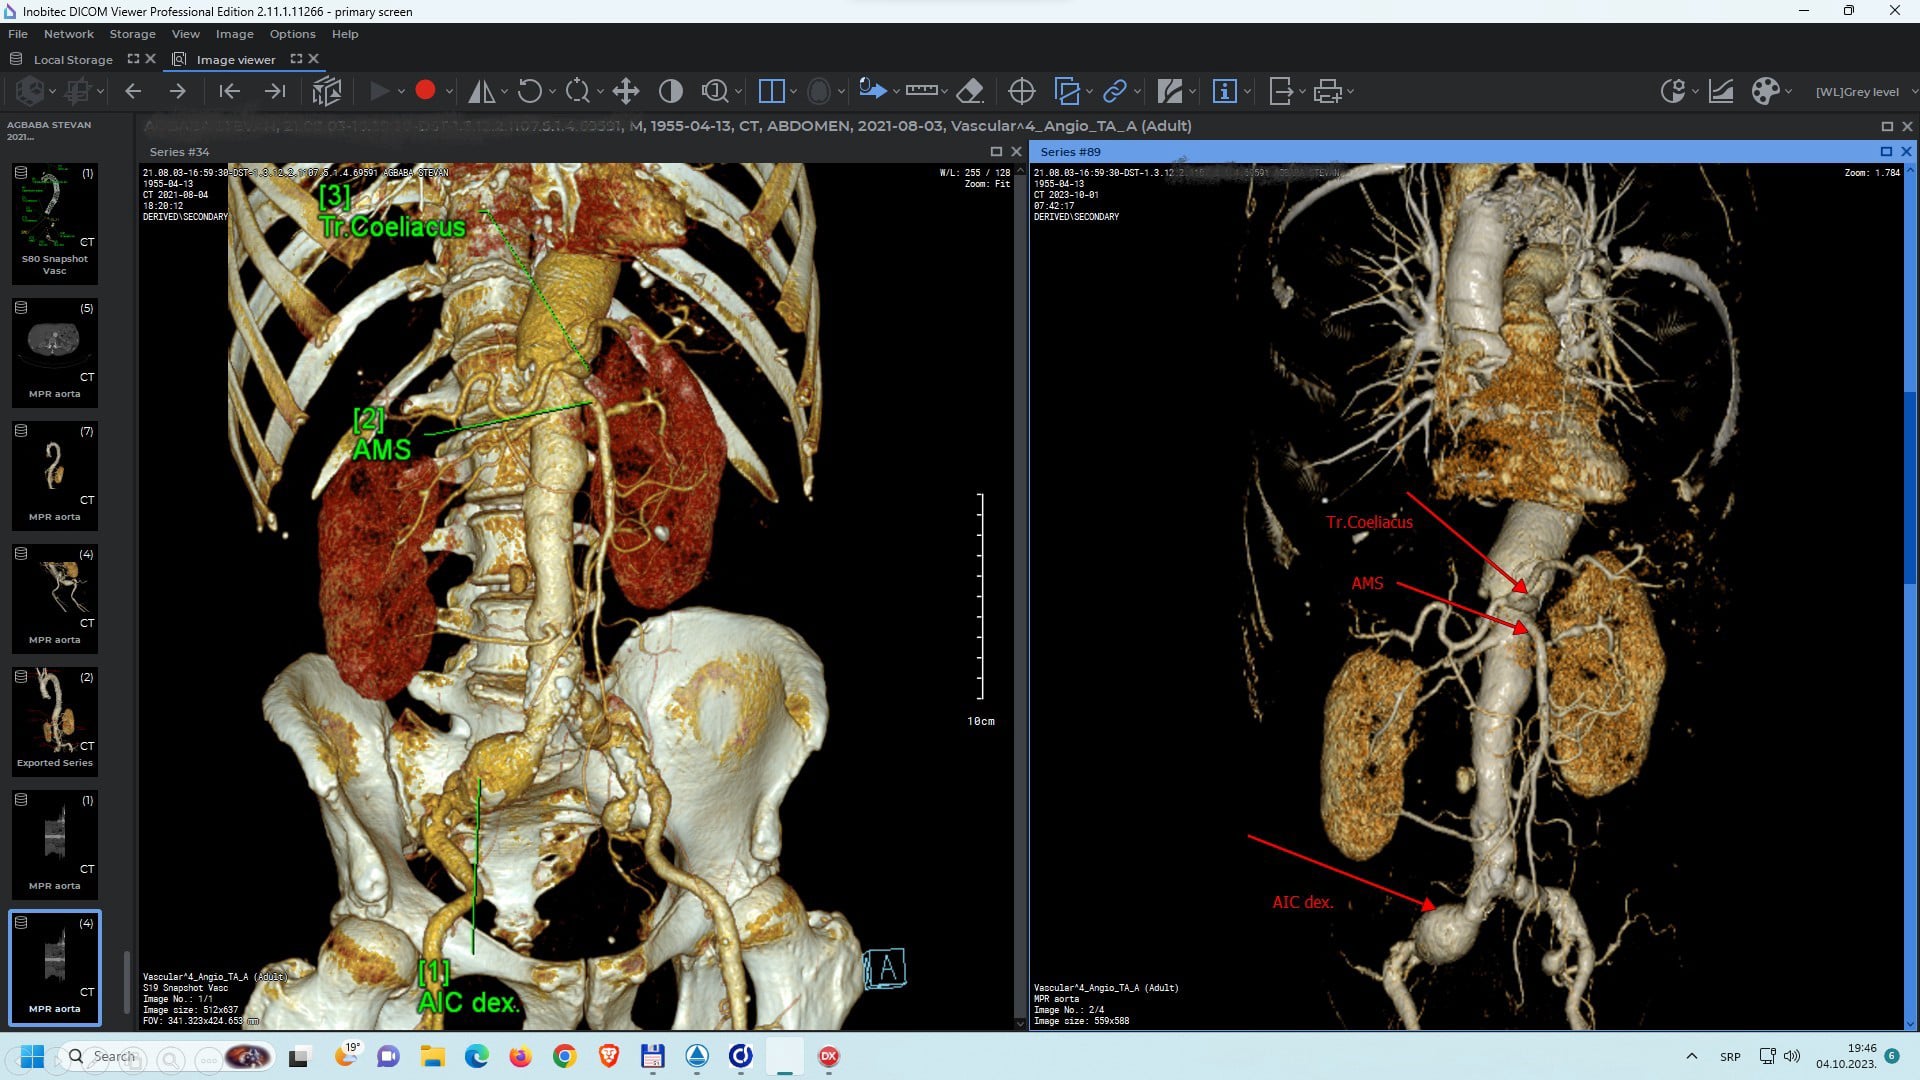

https://inobitec.com/eng/downloads/dicomviewer/